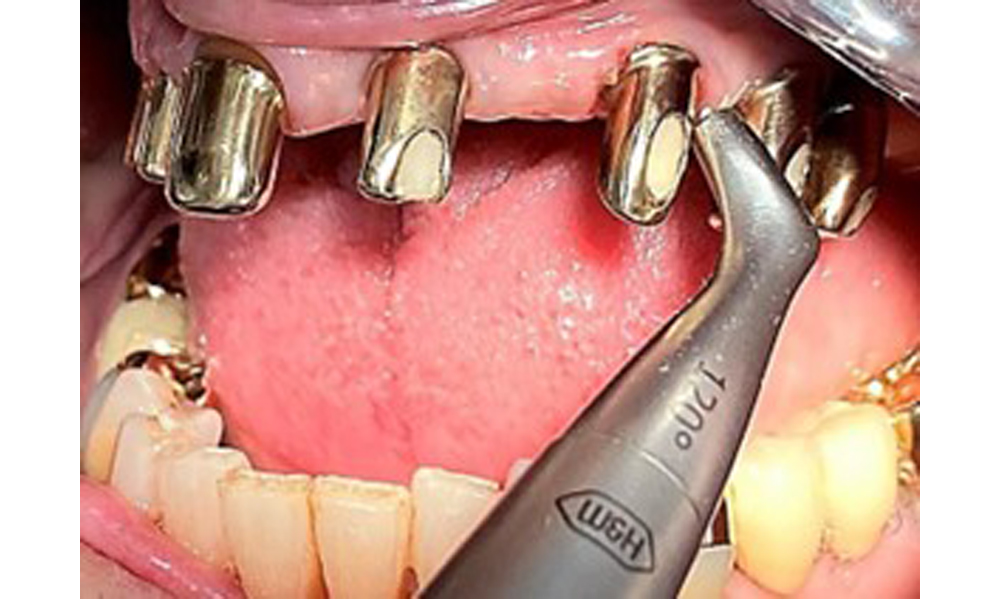

На пациентката е поставена комбинирана подвижна горночелюстна телескопична протеза преди повече от 25 години (фиг. 1, фиг. 2, фиг. 3) и тя е много доволна от протезите си. Пациентката има адекватна фиксирана протеза за долната челюст (фиг. 4).

Денталните открития са следните: Комбинирани снемаеми протези на импланти и телескопични протези, поддържани от зъби, на импланти 15, 13, 21, 23, 24, 25 и зъб 11 (фиг. 1, фиг. 2, фиг. 3). Пациентът е снабден с фиксирана долночелюстна протеза. Над зъби 37-34 и 45-47 бяха налични адекватни мостове (фиг. 4), краищата на коронките бяха интактни и нямаше активен кариес. Върху зъб 43 имаше композитна пломба с маргинална празнина. Имаше рецесия на долната гингива, която разкриваше от 1 до 3 mm от кореновата повърхност. Това се отнася и за 11.